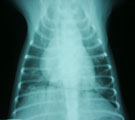

初診時。膿性鼻汁と湿咳あり。重度の肺機能低下 胸部レントゲン。左右の肺野後部に淡い浸潤影。 気管支鏡所見。左後葉気管支内に粘稠分泌物 治療開始2ヶ月後。肺機能は正常化し元気になった。

経過:受診時、膿性鼻汁と湿咳ありやや呼吸困難を示した。血液検査ではリンパ球増加ありジステンパーを肯定できなかった。胸部レントゲンでは左右の肺野後部に淡い浸潤影がみられた。動脈血酸素分圧は著しく低下し(PaO2 58.2 mm Hg)、重度の肺機能低下を示した。肺感染症が疑われその病原体診断のため気管支鏡検査を行った。気道粘膜全体にわたり浮腫著明であった。LB2,LB2D1,LB2V1,LB2V2, LB2D2入口部より粘稠分泌物が湧き出てきた。BAL(LB2V1)の回収率は9%ときわめて低かったが、総細胞数が4405 /μLと著しく増加しその91.5%は好中球であった。典型的な急性好中球性炎症パターンであった。また回収液からBordetella bronchiseptica が1.0×10CFU/ml検出され、ABPC, AMPC, CFPM, GM, AMK, MINO, OFLX, ENXに感受性、CEZ, CEX, CLDMに耐性を示した。下気道感染症(LRTI)と診断した。抗生剤と去痰剤投与を開始した。2ヶ月後には鼻汁と咳が完全に消失しPaO2 96.6 mm Hgと肺機能も正常化した。